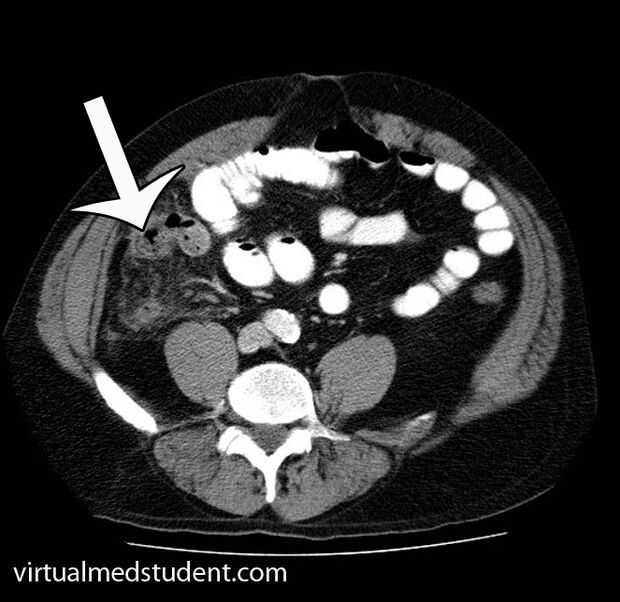

Cuando fui a la sala de emergencia, I descrito mis dolores de estómago al doctor, tiene una TC y muy rápidamente se le diagnosticó una ruptura del apéndice.